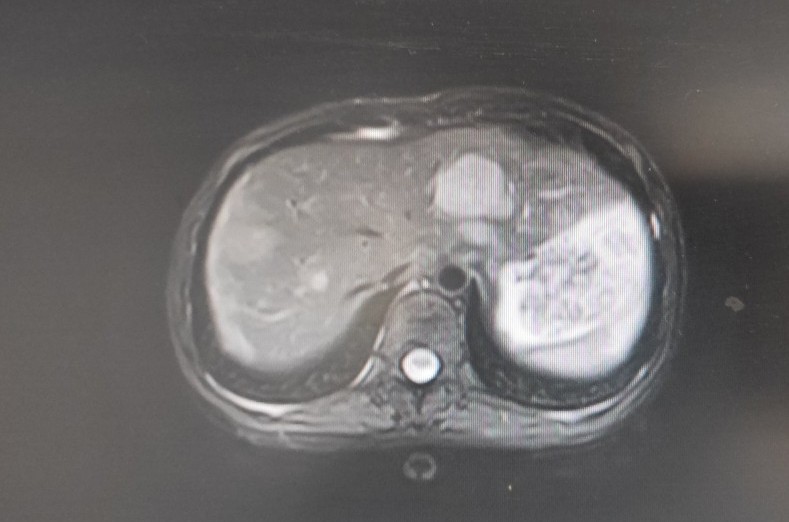

一位22岁的年轻女性,于2020年2月初诉下腹部隐痛,伴腹胀,乏力,就诊门诊妇科,查体发现左下腹一质硬包块,行盆腔核磁共振示:盆腔及子宫腔内多发占位。便收入院治疗,入院做上腹部CT示:肝脏多发低密度占位,考虑转移性病变。

入院后行手术治疗,术后病理:子宫内膜样癌,FⅠGOII级,侵及子宫壁全层,脉管内癌栓,双侧卵巢,左右宫旁,大网膜见癌累及。目前分期晚,预后差,需行术后辅助治疗。